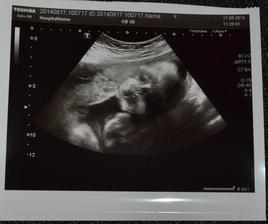

* 17.4.2014 kontrola v 10tt + 4 - kontrola dopadla skvěle. Nová paní doktorka je úžasná, mimčo má 4 cm, všechny nožičky a ručičky 🙂 .Vhledem k cukrovce v rodině jsem dostala žádanku na vyšetření. Odebraná krev na screening. Mimčo se nechtělo fotit, tak máme nic moc fotku 🙂 asi se stydělo...Termín máme 9.11.2014 (a 2.11. mám narozeniny, tak snad nebudu rodit na svoje narozky 🙂 ) A dostali jsme průkazku 🙂